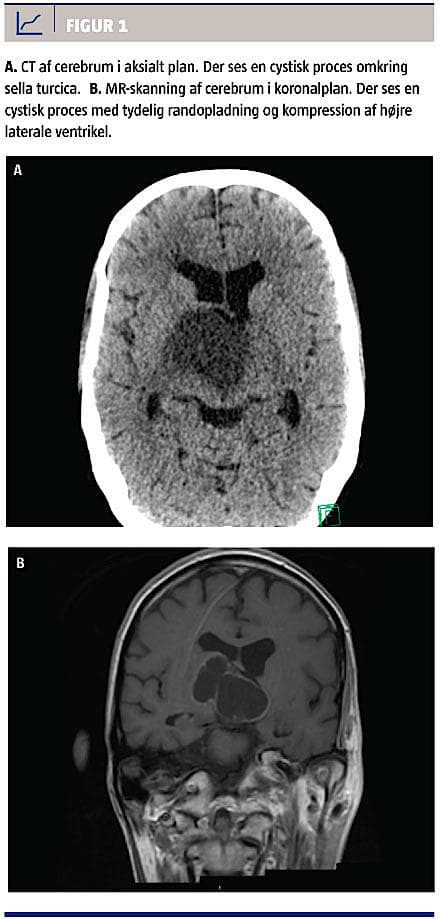

Han blev indbragt til skadestuen med stabile luftveje og vejrtrækning; der var sparsom kontakt og blæretemperaturen var 24,1 °C. Han var stabil i opvarmningsperioden, men efter perifer vasodilatation ved normotermi blev han tiltagende trykustabil, hvorfor der opstod mistanke om sepsis med ukendt fokus, og relevant behandling blev påbegyndt. I det akutte udredningsforløb blev der foretaget CT af thorax og abdomen samt lumbalpunktur. Alle testresultater var upåfaldende. Da patienten ikke initialt vågnede op

efter genopvarmning, blev der foretaget CT af cerebrum. CT’en viste en 3 × 4 × 6 cm stor central cystisk tumorproces med randopladning (Figur 1). Han fik stigende bevidsthedsniveau og blev med en Glasgow Coma Score på 14 overflyttet til en neurointensiv afdeling. Her blev der fundet endokrinologisk derangering af alle akser og svært nedsat syn. Tumoren blev herefter excideret succesfuldt, men i efterforløbet opstod der et intracerebralt hæmatom og hydrocephalus, EEG’et var abnormt, og der var betydelige iskæmiske forandringer i hjerneparenkymet. I samråd med familien afsluttedes den aktive behandling, og patienten afgik ved døden samme dag.